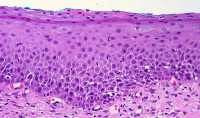

Еще одно исследование 2010 года, проведенное в Китайском Медицинском Университете, обнаружило, что, если мышам травмировать кожу, то в этом месте количество клеток с выраженными рецепторами CB1 возрастает. Увеличение числа таких клеток начиналось спустя шесть часов после травмы, достигало пика через пять дней после травмы и пришло к норме через две недели после травмы.

Сначала большинство клеток с экспрессией рецепторов CB1 на месте раны были мононуклеарными (то есть это были красные кровяные клетки и специализированные иммунные клетки моноциты), которые, как известно, участвуют в воспалительном процессе при иммунном ответе; спустя несколько дней начали преобладать уже фибробластические клетки (играющие жизненно-важную роль в заживлении ран и формировании рубцовой ткани. Хотя не ясно до конца, что именно здесь происходит, очевидно, что тут задействованы анадамид и рецепторы CB1.